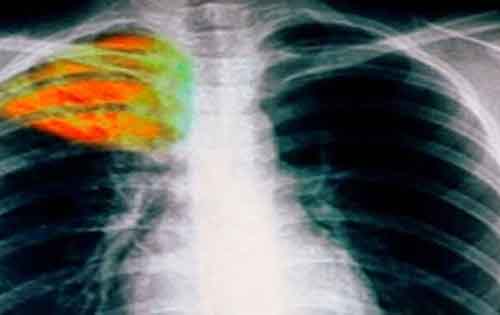

Ωρολογιακή βόμβα η φυματίωση στην Ελλάδα – Κάθε χρόνο 50 κρούσματα

Ωρολογιακή βόμβα αποτελεί για τη δημόσια υγεία της χώρας μας η πολυανθεκτική φυματίωση. Στο νοσοκομείο «Σωτηρία» όπου λειτουργεί ειδική Μονάδα για την αντιμετώπιση της λοιμώδους μεταδοτικής νόσου, καταγράφονται κάθε χρόνο περίπου 50 κρούσματα πολυανθεκτικής φυματίωσης, αριθμός που χαρακτηρίζεται μεγάλος από τους ειδικούς σε σύγκριση με τα αντίστοιχα περιστατικά των περασμένων …